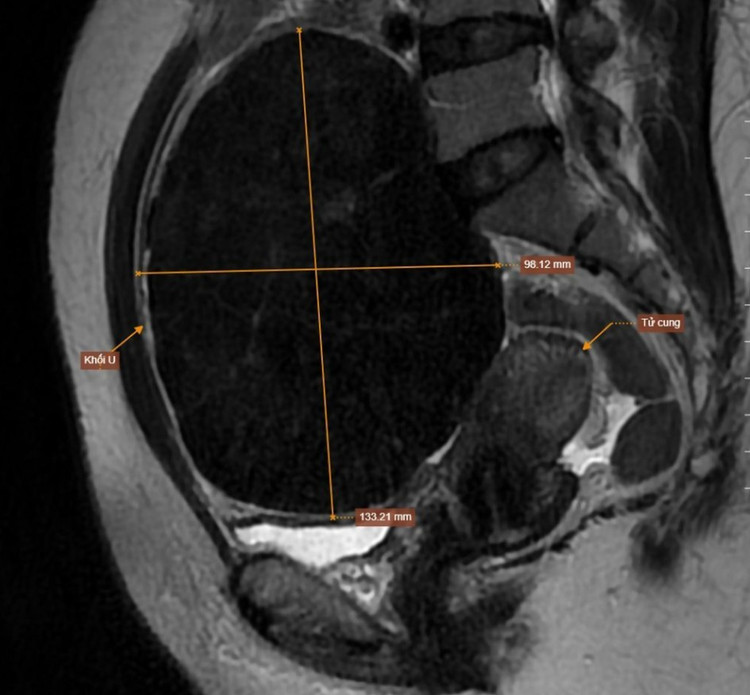

Kết quả siêu âm và MRI ghi nhận khối u xơ kích thước 98×133mm nằm lệch trái vùng tiểu khung, choáng gần toàn bộ không gian ổ bụng.

Khối u tử cung choán gần hết ổ bụng bệnh nhân - Ảnh BVCC